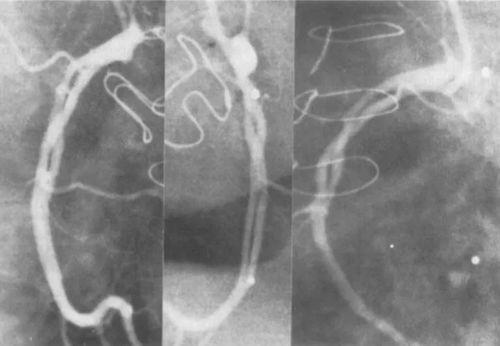

2. 血管检查:血管造影可以帮助医生发现血管的病变,如动脉瘤、血管瘤等。